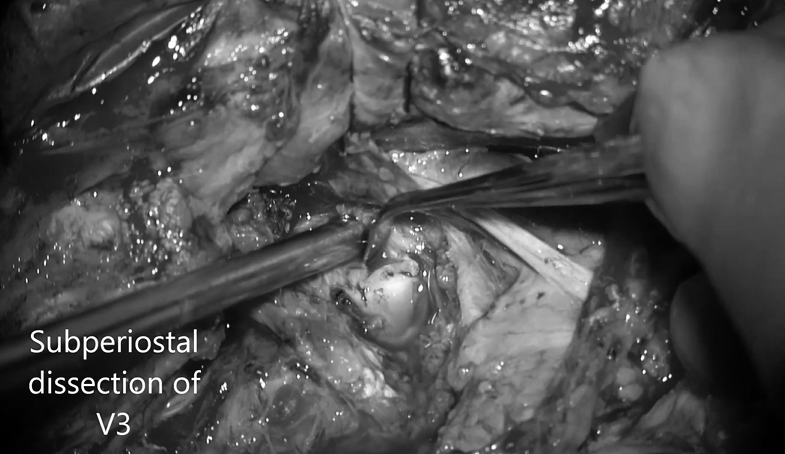

▼颅外椎动脉V3段骨膜下剥离术解剖动脉,保留静脉丛